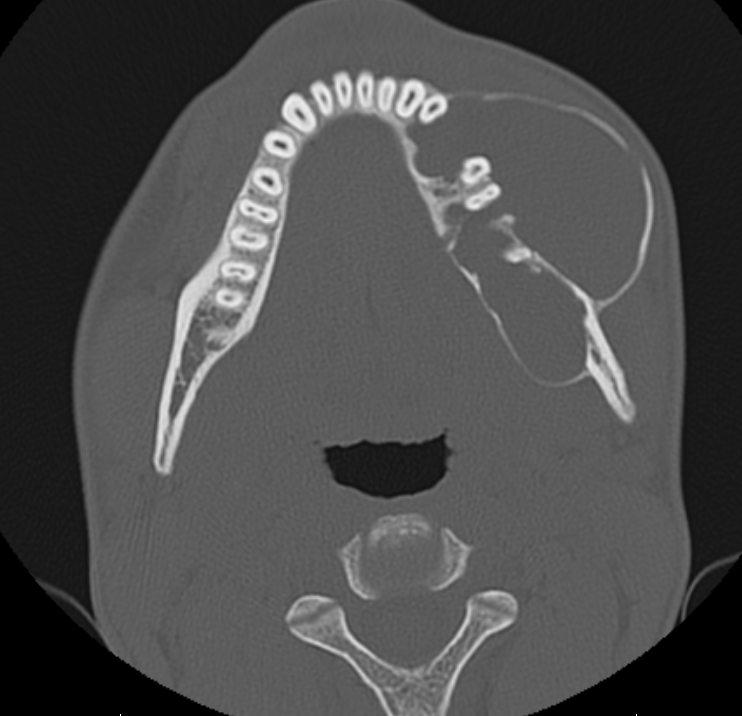

There is an expansile lytic heterogeneous soft tissue lesion centred on the left mandibular angle with cortical thinning and areas of cortical breach. The lesion measures approximately 6.6 x 3.6 x 3.8 cm.

NCCT features are suggestive of Ameloblastoma.

NCCT face features are suggestive of large expansile lytic soft tissue lesion of left mandible – ?Ameloblastoma.